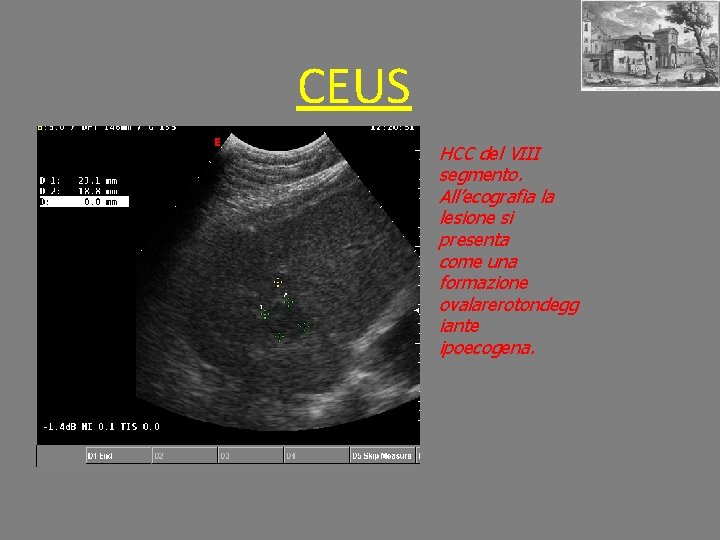

CEUS HCC del VIII segmento. All’ecografia la lesione si presenta come una formazione ovalarerotondegg iante ipoecogena.